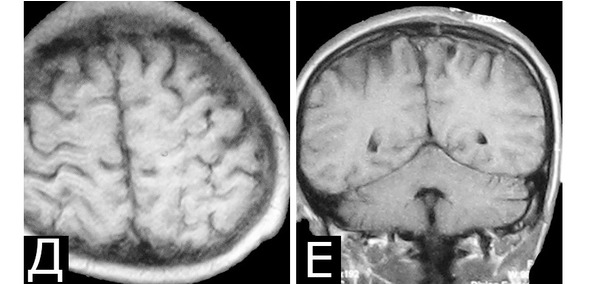

Послеоперационное течение: В послеоперационном периоде нарастания неврологической симптоматики не было. При осмотре спустя 3 года после операции очаговой неврологической симптоматики нет. Сохраняются редкие парциальные приступы в виде тонических судорог в правой ноге. По данным МРТ, КМ удалена полностью (Д, Е). Рекомендован дальнейший постоянный прием антиконвульсантов.

Рис. 58.I. Электростимуляция моторной коры на операции

Рис. 58.II. Электростимуляция моторной коры на операции

Рис. 58.III. Электростимуляция моторной коры на операции. Объяснения в тексте